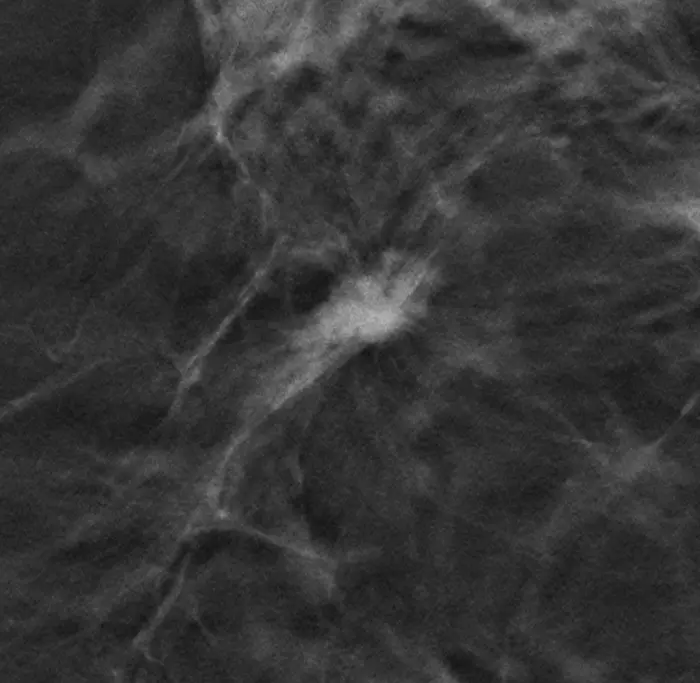

A combination of DBT - short for Digital Breast Tomosynthesis - and Synthetic 2D Mammography (SM) was used for the almost 100,000 TOSYMA study participants. The interdisciplinary study group led by Prof. Walter Heindel, Director of the Clinic for Radiology at the University Hospital Münster, compared the data obtained with the combined procedure - known as DBT+SM - with that from conventional screening with digital mammography (DM). The result: DBT+SM leads to the detection of significantly more invasive breast cancers compared to the conventional DM procedure. However, this does not necessarily mean that women’s health is improved – the keyword here is overdiagnosis. In other words, it has been shown that DBT+SM "finds" breast cancer better - but the task now was to investigate whether this can be expected to actually lead to an improvement for the affected breast cancer patients.

In an exploratory subanalysis, Prof. Stefanie Weigel, Prof. Walter Heindel and Prof. Hans-Werner Hense examined which tumors are frequently detected at an earlier stage of breast cancer - and found that DBT+SM screening can detect relevant tumors, i.e. those that - in contrast to less aggressive variants - are potentially relevant for a reduction in breast cancer mortality. Prof. Stefanie Weigel concludes: "From the results of the subanalysis, we conclude that the higher rate of early tumor stages of tumor grades 2 and 3 through the use of DBT+SM could increase the screening effect with regard to breast cancer mortality" - another "plus point" for DBT+SM.